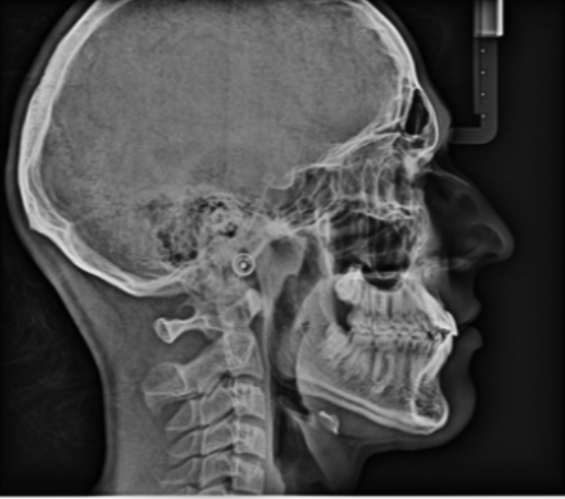

How do I convince my ortho to give me a palate expander reverse pull headgear and Herbst appliance my mandible itself is recessed slightly so I think I can get the Herbst appliance prescribed but the palate expander and reverse pull headgear would also be very beneficial for me since my palate isnt that wide its bare minimum and my maxilliary forward growth is horrible honestly. this is my xray btw